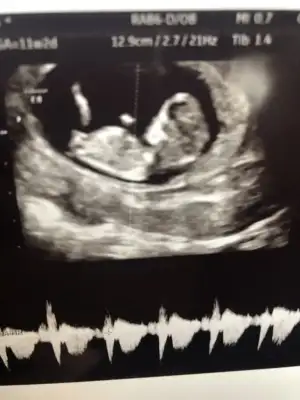

Teşekkürler uc tane usg var şuan elimde bgnun paylaşıyorum hemen, heyecanla yorumunuzu bekliyorum 😊😊😊💕

• 20200127_195645_HDR.webp

20200127_195645_HDR.webp

13,7 KB · Görüntüleme: 34

Evet ilk hayırlısıyla 12 de tekrar paylasicam bakalim degisiklik olucak mi 😊 hislerim erkek yonunde isteğimse kız kısmet artık